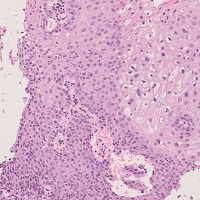

扁平上皮癌